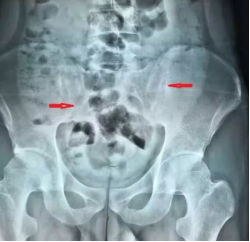

同年4月份大腿内外侧和腹股沟区均出现疼痛,且左下肢跛行,在家人的陪伴下,遂前往市专科医院,经系统专项检查:x片显示骶髂关节炎侵犯双侧髋关节,磁共振检查显示髋关节积液,诊断为骶髂关节炎、髋关节滑膜炎。

双侧骶髂关节密度不均,关节间隙似乎不等、双侧髋关节包容欠佳,从磁共振上看关节内大量积液